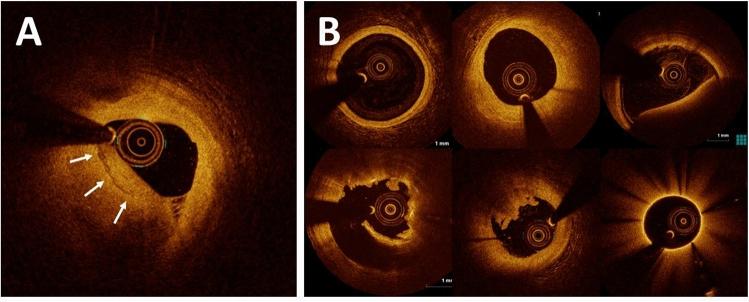

Healed coronary plaques, morphologically characterized by a layered phenotype, are signs of previous plaque destabilization and healing. Recent optical coherence tomography (OCT) studies demonstrated that layered plaque is associated with higher levels of local and systemic inflammation and rapid plaque progression. However, the diagnosis of layered plaque needs expertise in OCT image analysis and is susceptible to inter-observer variability. We developed a deep learning (DL) model for an accurate diagnosis of layered plaque. A Visual Transformer (ViT)-based DL model that integrates information from adjacent frames emulating the cardiologists who review consecutive OCT frames to make a diagnosis was developed and compared with the standard convolutional neural network (CNN) model. A total of 237,021 cross-sectional OCT images from 581 patients collected from 8 sites were used for training and internal validation, and 65,394 images from 292 patients collected from another site were used for external validation. In the five-fold cross-validation, the ViT-based model provided better performance (area under the curve [AUC]: 0.860; 95% confidence interval [CI]: 0.855-0.866) than the standard CNN-based model (AUC: 0.799; 95% CI: 0.792-0.805). The ViT-based model (AUC: 0.845; 95% CI: 0.837-0.853) also surpassed the standard CNN-based model (AUC: 0.791; 95% CI: 0.782-0.800) in the external validation. The ViT-based DL model can accurately diagnose a layered plaque, which could help risk stratification for cardiac events.